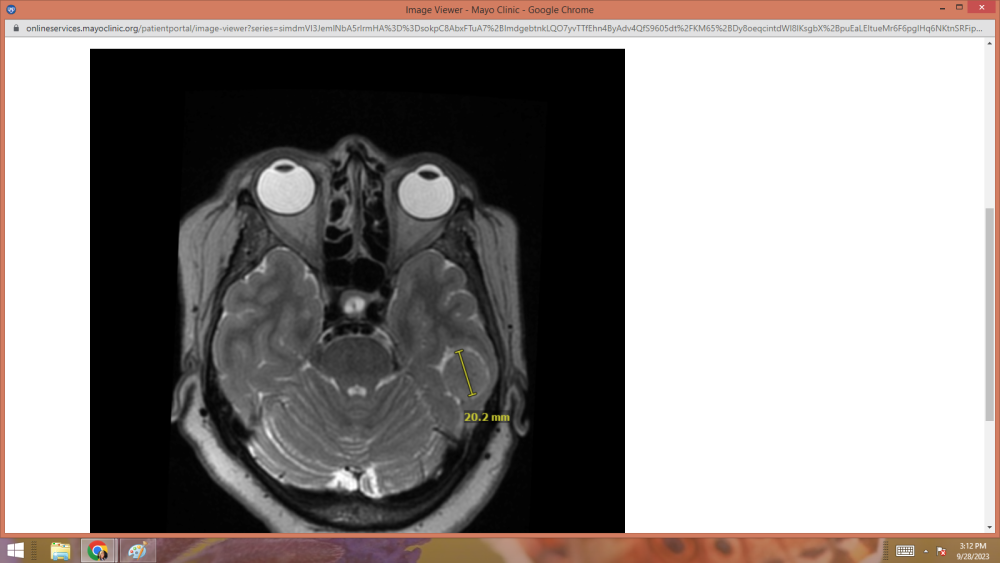

UPDATE:     GOOD NEWS!!!   My tumor hasn't grown any since 2019.

Thank you brothers and sisters for the prayers.    They were felt.

scan1.png

scan2.png

scan3.png

scan4.png